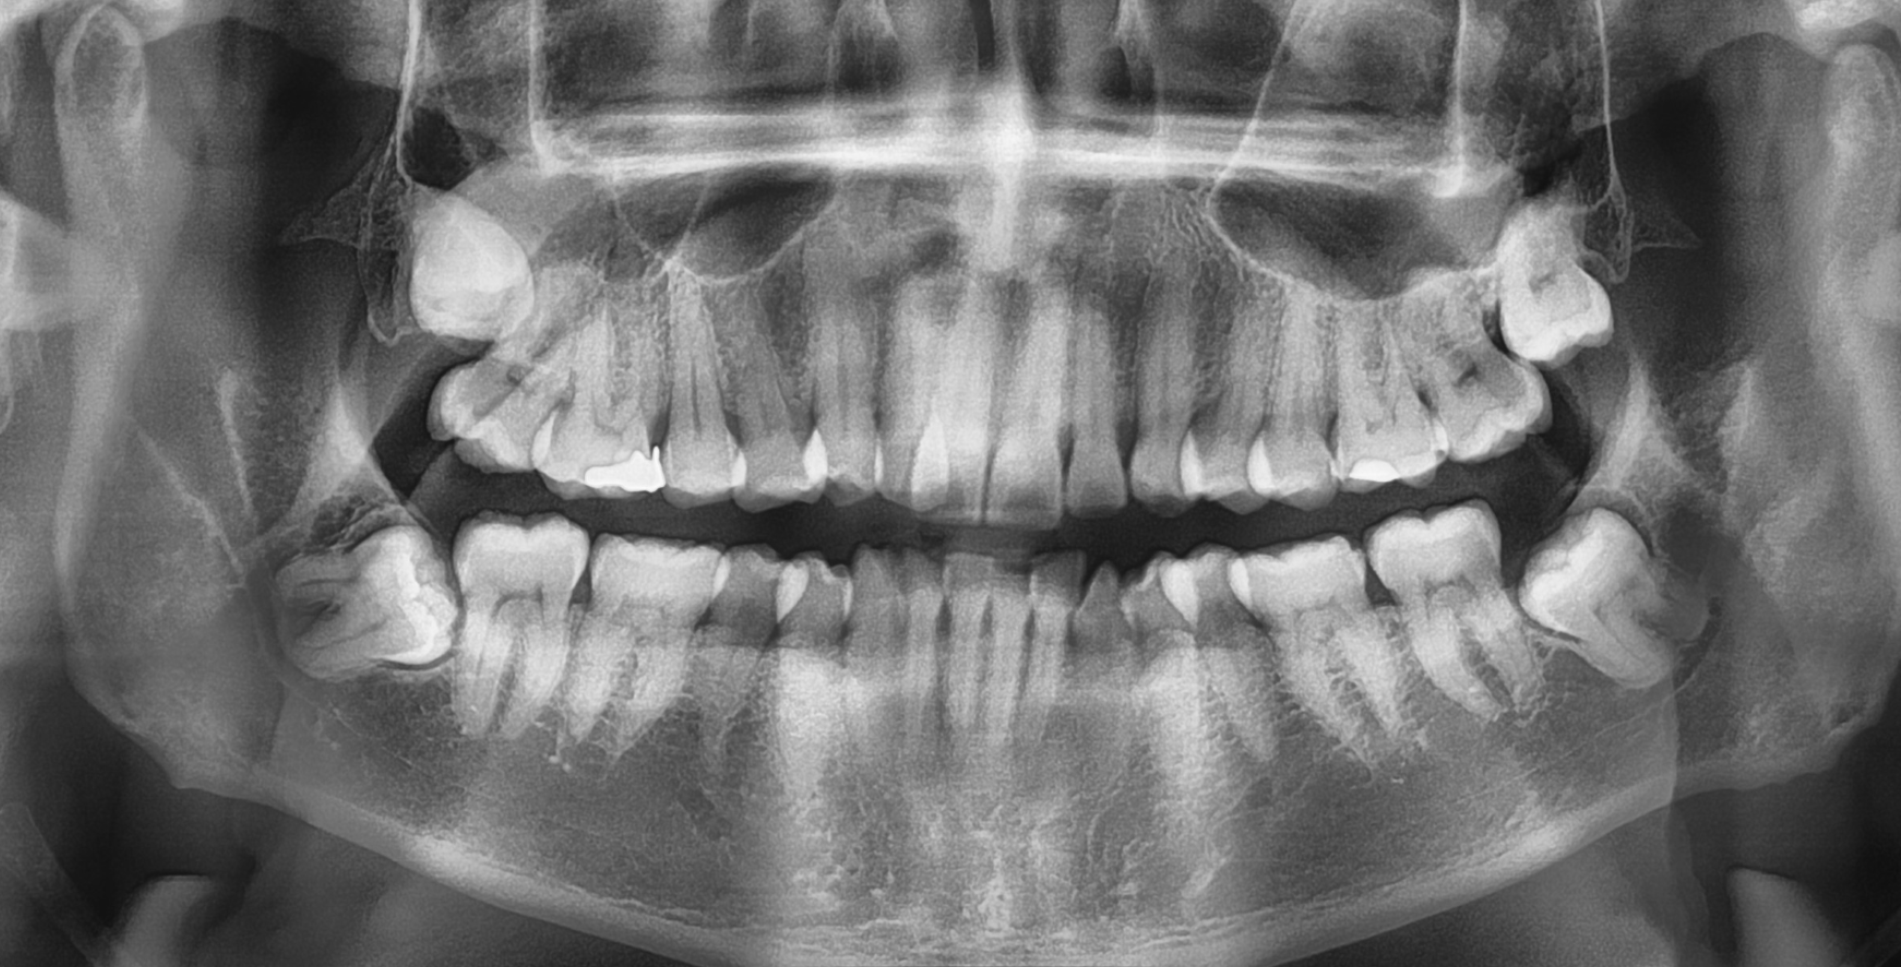

The main reason you may need to see an Oral Surgeon is for impacted wisdom teeth. While the majority of wisdom teeth erupt into the mouth uneventfully between the ages of 18-25 this is not always the case.

Sometimes wisdom teeth do not have suffiecient room to erupt fully, these are called impacted. Impacted teeth can sometimes lead to painful infections as well as food packing, which in turn can lead to decay. Sometimes this decay is in the adjacent tooth.

Lower wisdom teeth lie in close proximity to a nerve that supplies sensation to your lower lip, chin and teeth (Inferior Dental Nerve) as well as a nerve that supplies sensation to your tongue.